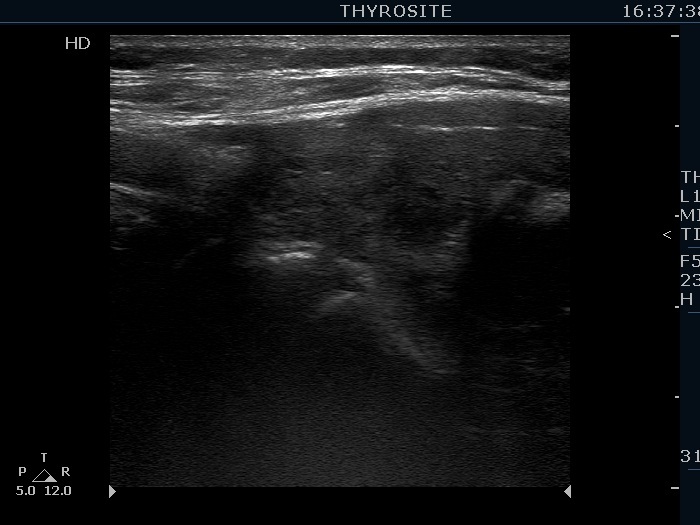

Consecutively operated patients with autoimmune thyroid disease - case 9 (1681)

Follow-up investigation 23 months after the first visit (ultrasonographic picture 5)

The patient is euthyroid without thyrostatic therapy

Left lobe, longitudinal scan.